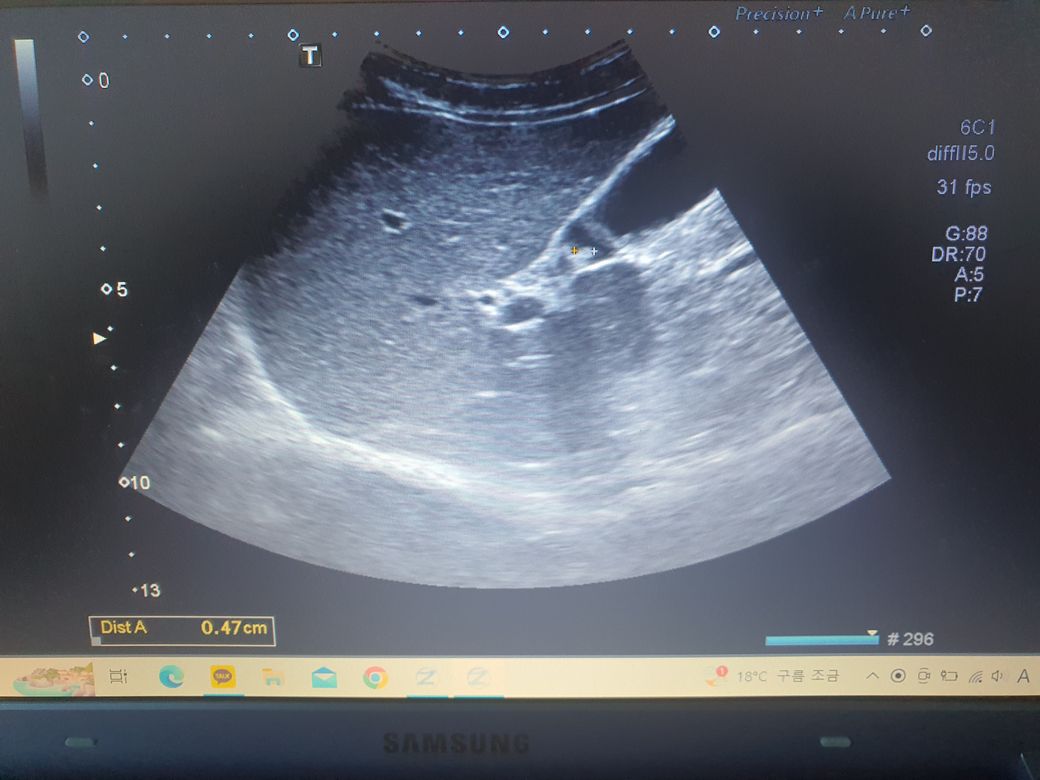

용종 크기: 4.7mm

• 1번 째 사진